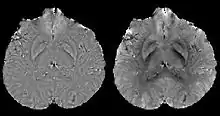

A unique advantage of MRI is that it provides not only the phase image but also the magnitude image. In principle, the contrast change, or equivalently the edge, on a magnitude image arises from the underlying change of tissue type, which is the same cause for the change of susceptibility. This observation is translated into mathematics in MEDI, where edges in a QSM which do not exist in the corresponding magnitude image are sparsified by solving a weighted norm minimization problem.[14]

MEDI has also been validated extensively in phantom, in vitro and ex vivo experiments. In in vivo human brain, MEDI calculated QSM showed similar results compared to COSMOS without statistically significant difference.[15] MEDI only requires a single angle acquisition, so it is a more practical solution to QSM.